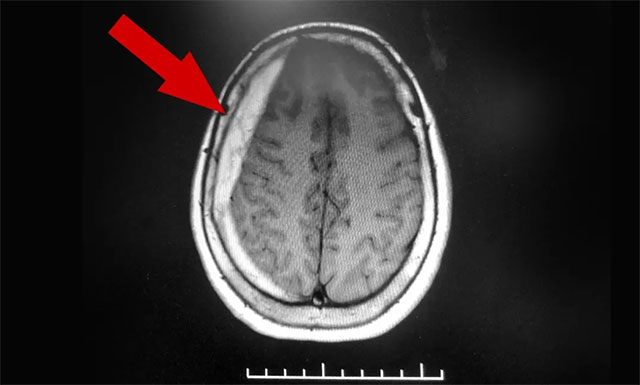

今年6月,82岁的金阿婆(化名)因脑梗至上海某医院救治,所幸没有大碍。然而到了9月份,金阿婆感到持续性头痛发作,且有不断加重的趋势。她以为脑梗又犯了,便慕名来到上海蓝十字脑科医院寻求进一步治疗。医院神经内科专家李淑琴医生在门诊为金阿婆完善相关影像学检查后发现,患者右侧额颞部颅骨内板下方呈新月形高密度影,是硬膜下血肿的典型影像表现。

▲ 患者右侧额颞部颅骨内板下方呈新月形高密度影